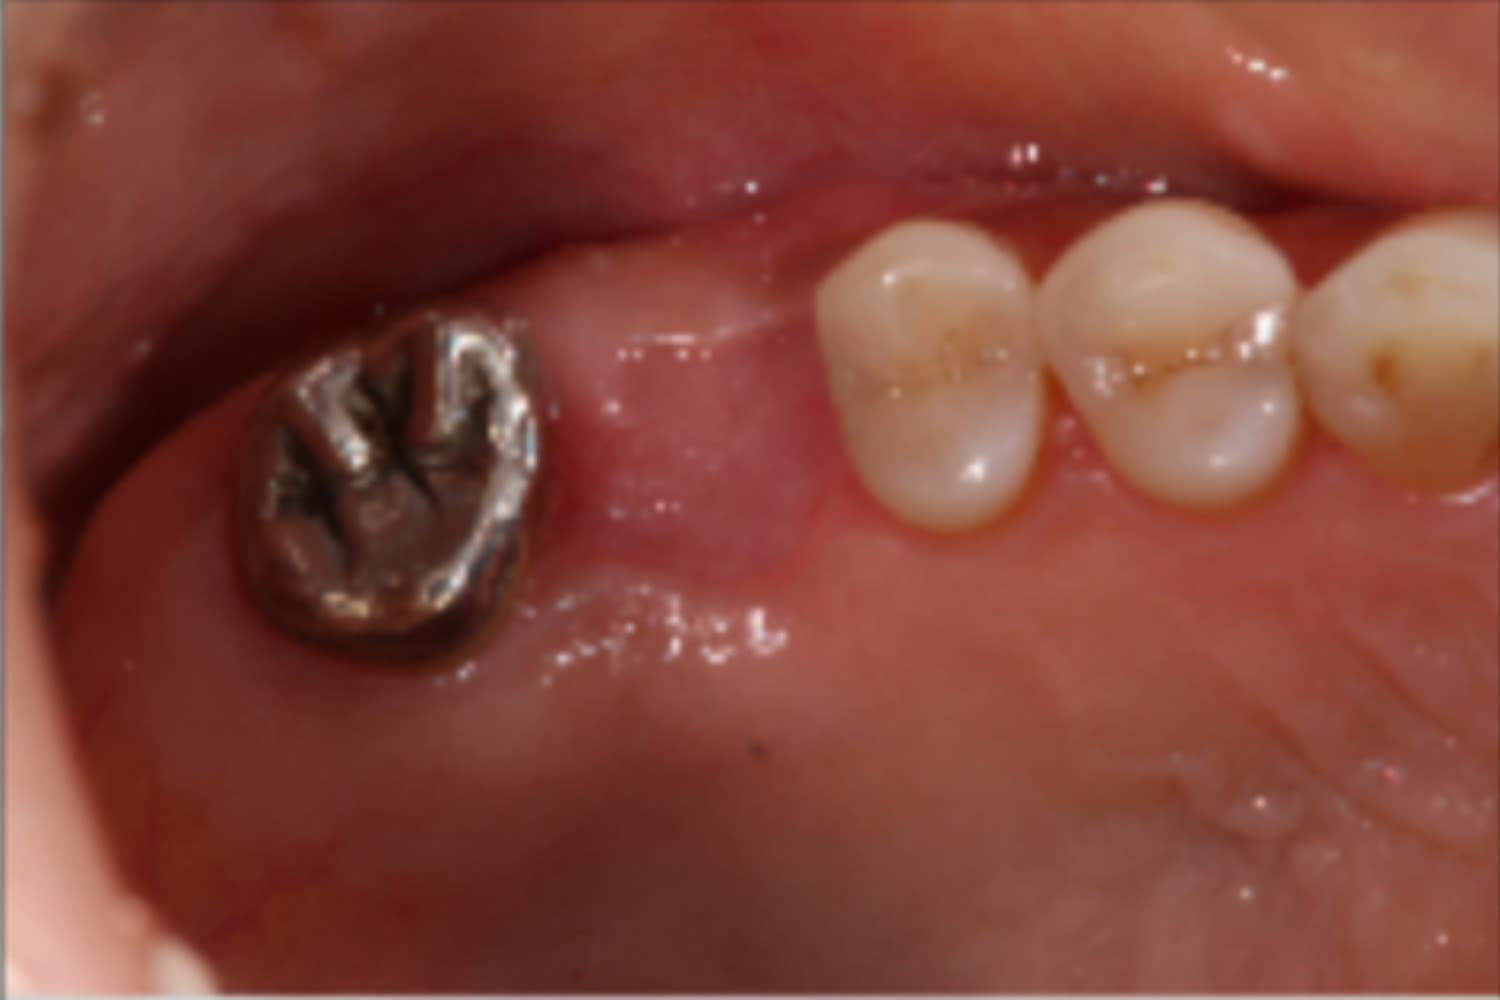

右上欠損部のインプラント治療

Before

右上欠損部にインプラント治療を行なった

右上歯牙欠損部にインプラント治療希望